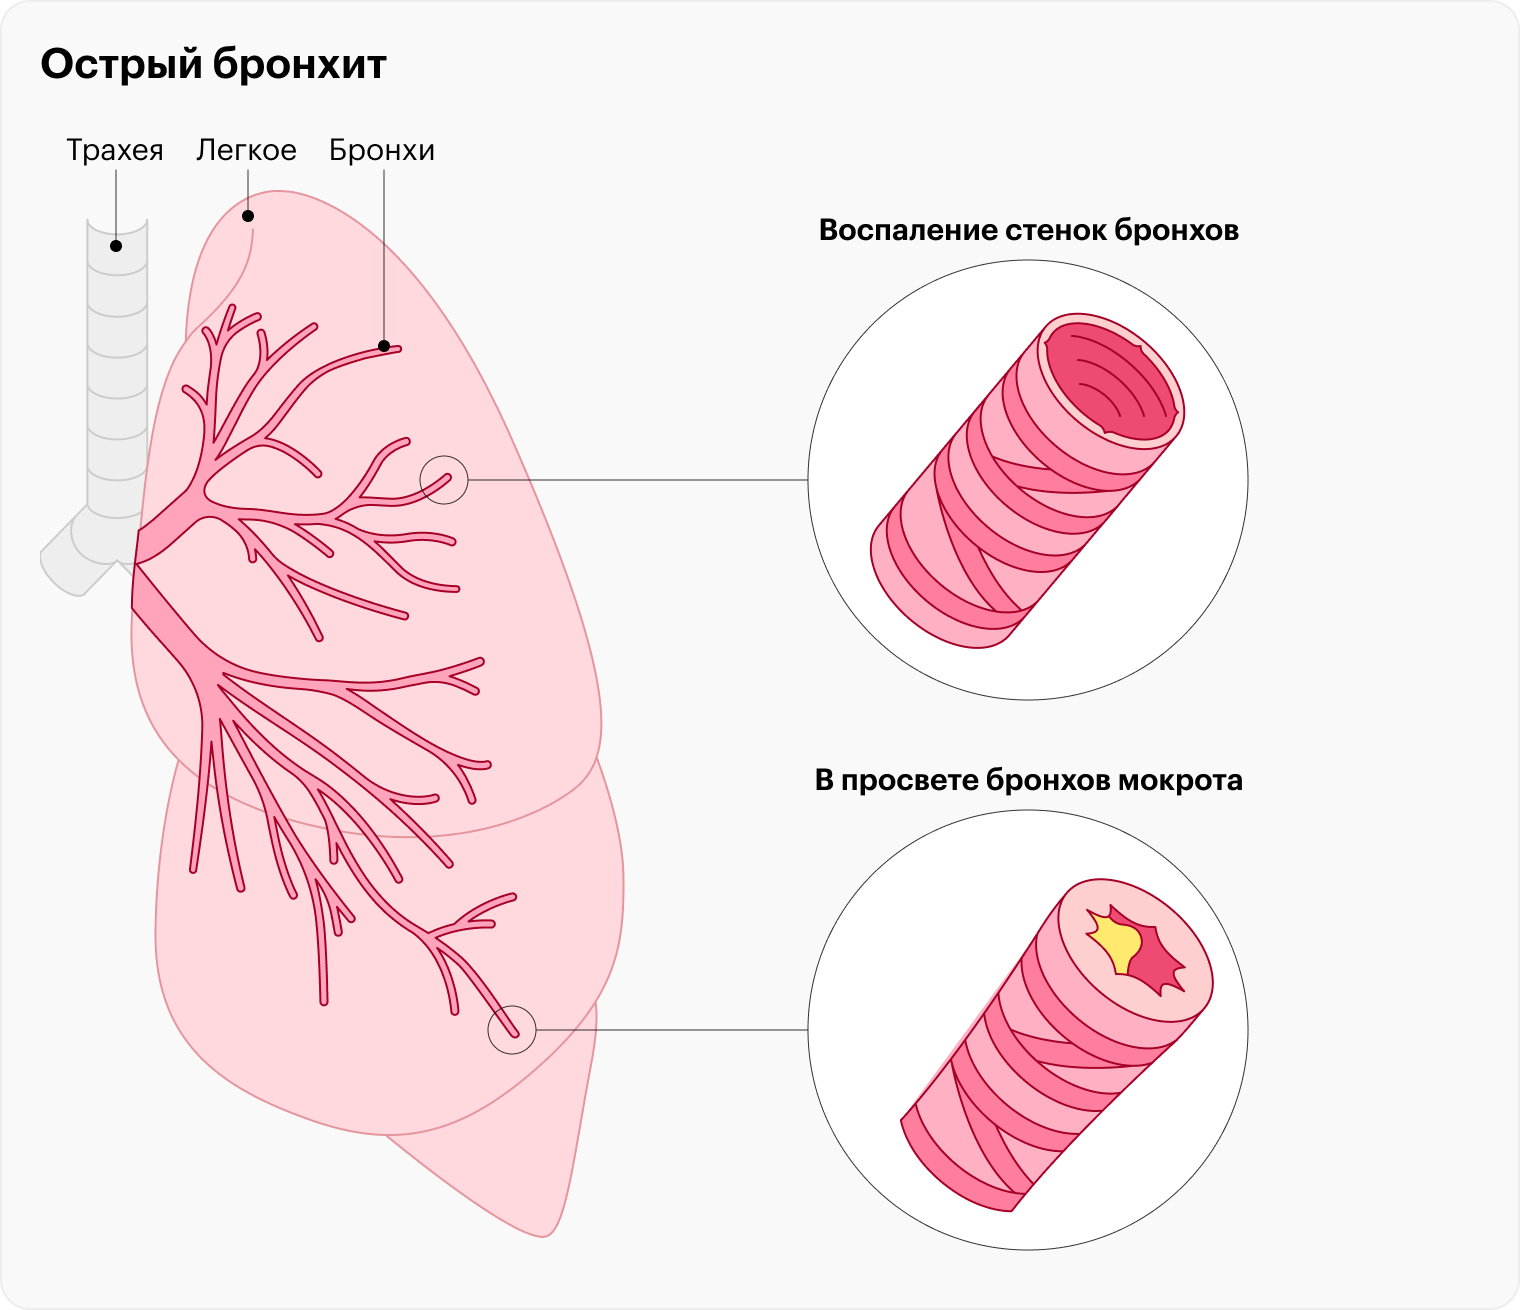

Еда для Легких и Бронхов - Полезные Рецепты